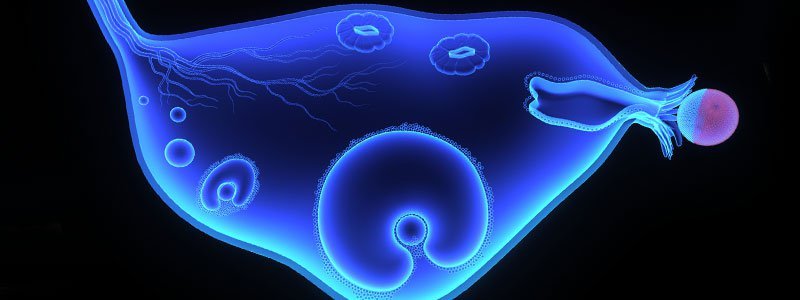

A:Fibroids (also called leiomyomas or myomas) are a type of muscular tumors that grows within the uterus (womb), in the uterine wall, or on the outside surface of the uterus.

Women may develop a single uterine fibroid, or there may be many. Fibroids can vary widely in size and can be so small they are invisible to the naked eye or even as large as a grapefruit or bigger.